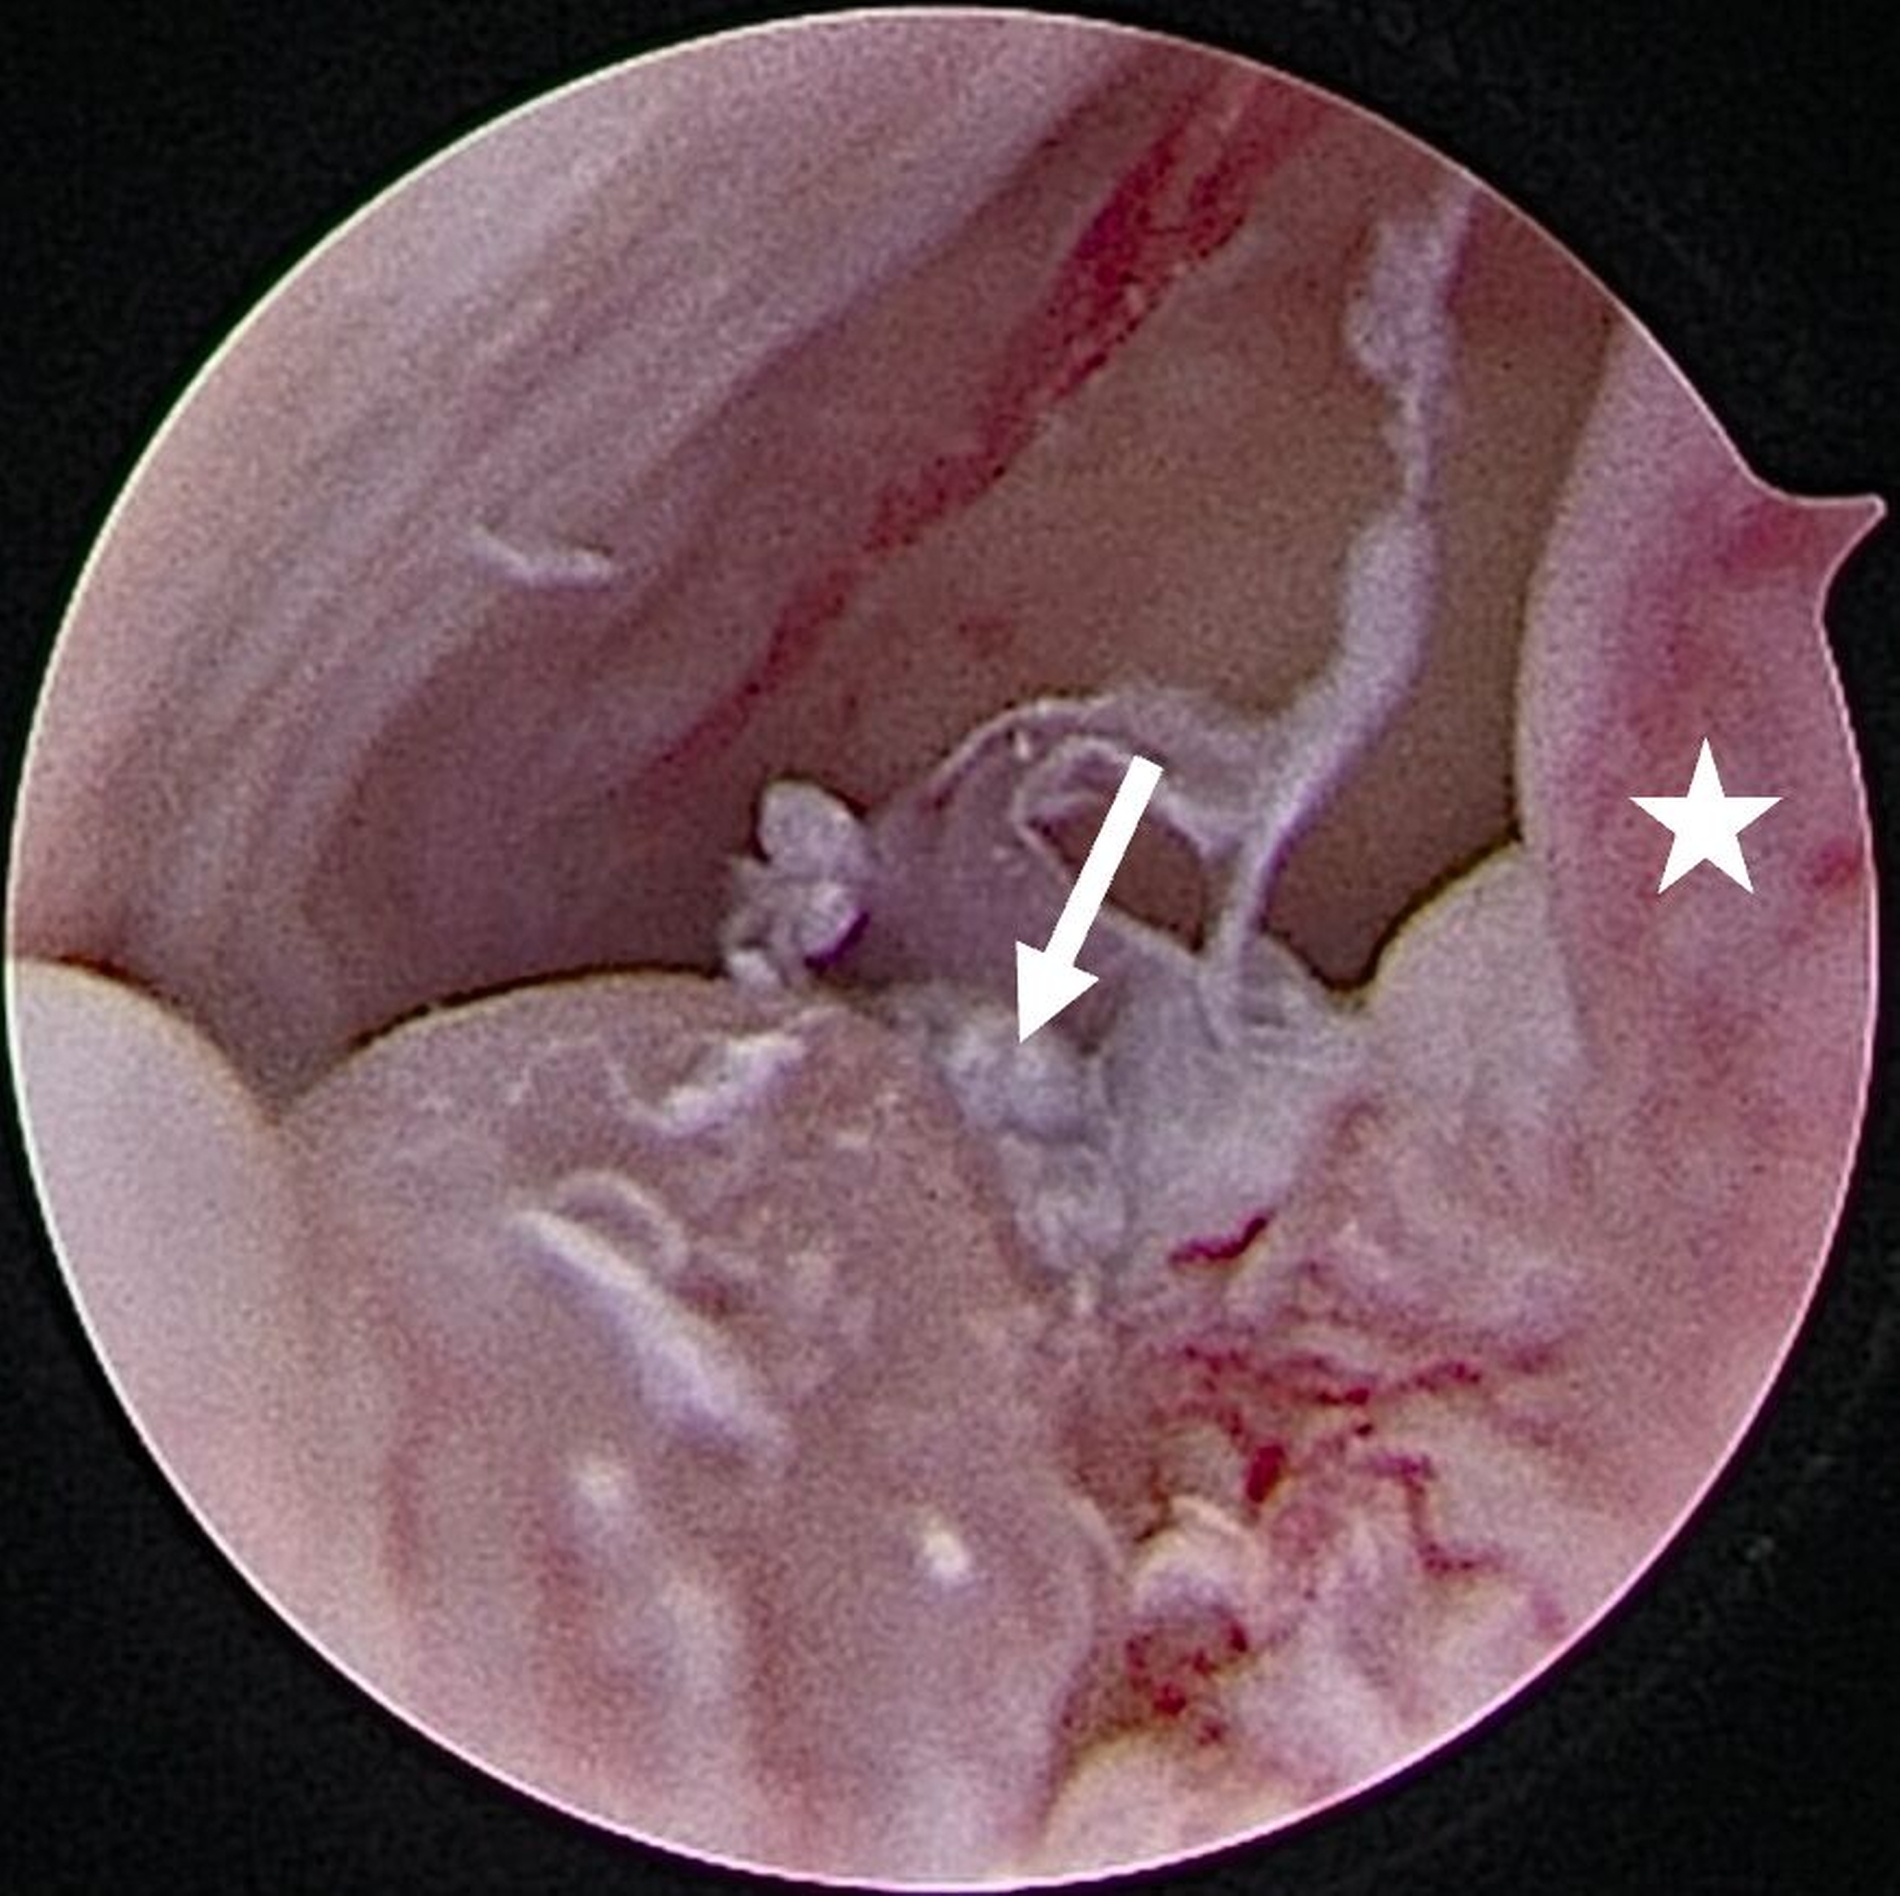

Die Level-II- (Abbildung 4a) beziehungsweisedie Level-III-Arthroskopie beinhalten zusätzlich einen zweiten beziehungsweise einen dritten Zugang über den beispielsweise Verwachsungen entfernt (Abbildung 4b) oder auch Biopsien entnommen werden können. Darüber hinaus ermöglichen diese die Durchführung eines sogenannten „anterior release“ (Abbildung 5). Darunter versteht man das arthroskopische Durchtrennen des vorderen Aufhängungsbandes des Diskus, wodurch dessen Beweglichkeit verbessert werden kann. Auf diese Weise kann der Diskus (unter anschließender konservativer Therapie) wieder in eine physiologischere Position zurückgleiten. Darüber hinaus können auch weiterführende Eingriffe wie Diskopexien durchgeführt werden, also die arthroskopisch gestützte Reposition und Fixation des Diskus in anatomisch korrekter Position [McCain, 1988].

Für intraartikuläre Eingriffe wird häufig die sogenannte Coblation-Technik genutzt (Coblation: Kofferwort aus Controlled Ablation). Diese Technik steht für ein minimalinvasives chirurgisches Verfahren, mit dem durch ein Niedrigtemperaturplasma Gewebe abgetragen werden kann. Im Gegensatz zu thermischen Verfahren wie Laser oder Elektrokaustik arbeitet die Coblation mit Temperaturen zwischen nur 40 bis 70 Grad Celsius. Dadurch kann Gewebe präzise entfernt werden, ohne dass umliegende Strukturen (durch zu hohe Temperaturen) geschädigt werden [Chen et al., 2010].